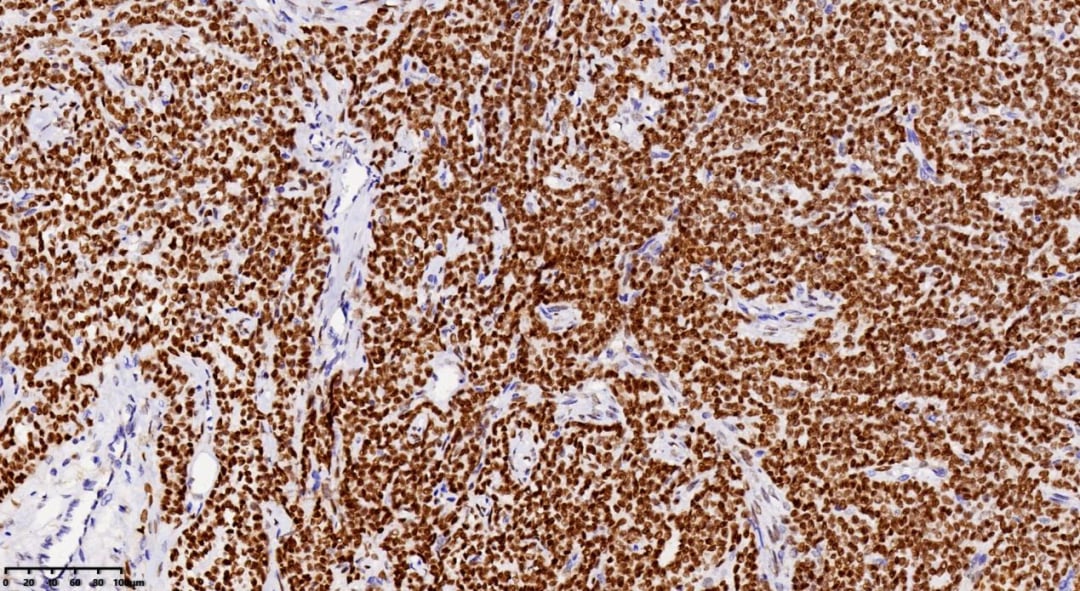

免疫组化结果:分子层面的证据

为了进一步明确诊断,进行了免疫组化染色。结果显示:

FOXL2

CD56

Inhibin α

Vimentin

免疫组化与分子病理学:FOXL2基因的关键作用

- 免疫组化:AGCT通常表达性索分化标记物,如inhibin、calretinin、CD99、类固醇生成因子(SF-1)和WT1。其中,α-inhibin的特异性优于Calretinin。

- FOXL2基因:值得注意的是,高达97%的AGCT病例表达FOXL2。更重要的是,超过90%的AGCT存在FOXL2基因点突变,这一突变被认为是AGCT发生发展的重要驱动因素。

- 其他常见阳性标记物包括CD56、vimentin、S100、SMA、CD10(通常弱阳性)。间质成分可表达desmin。CK灶状阳性,而CK7、CK20和EMA通常为阴性。